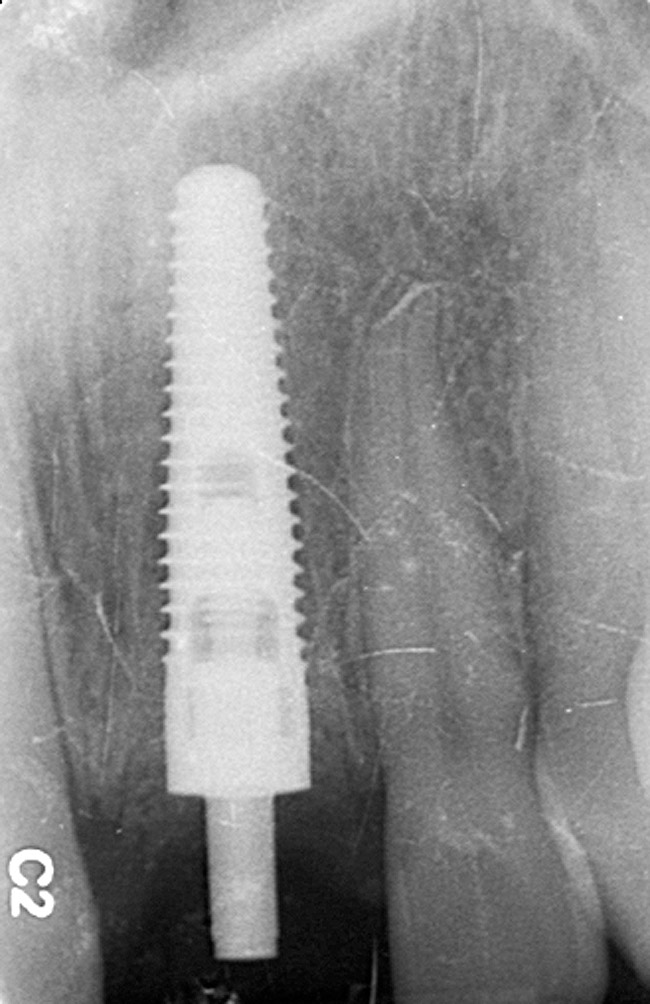

Figure 15  Regular-platform 4.3-mm x 16-mm implant positioned in osteotomy—periapical view.

Figure 15

The periodontist positioned a 4.3-mm x 16-mm regular-platform implant flush with the facial crest and 1 mm subcrestally interproximally (Figure 15), with a manually driven final seating torque value > 50 Ncm, followed by hand-tightened attachment of the immediate temporary abutment.